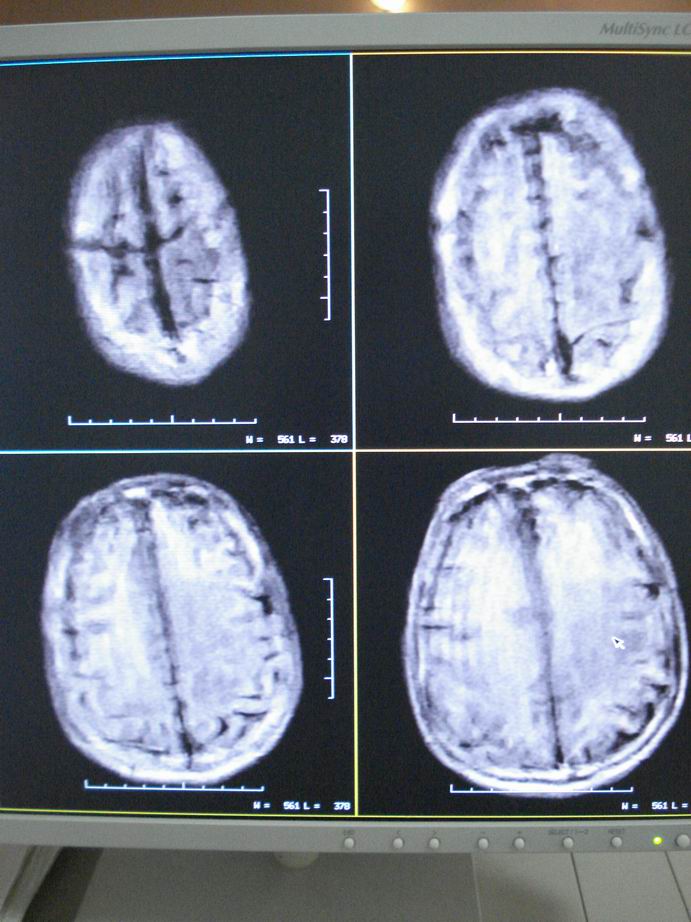

男60岁,左侧肢体乏力及精神异常10天,血压正常,血常规,肝肾功正常,腰穿无异常,请教颅内多发病灶,考虑什么?感染?肿瘤(转移性?)还是其它?

考虑为颅内多发转移瘤

脑内多发性转移瘤。

淋巴瘤较转移瘤可能大。

脑内多发占位性病变,首先考虑感染性病变,其次是转移瘤。

结合病人高龄,考虑转移瘤